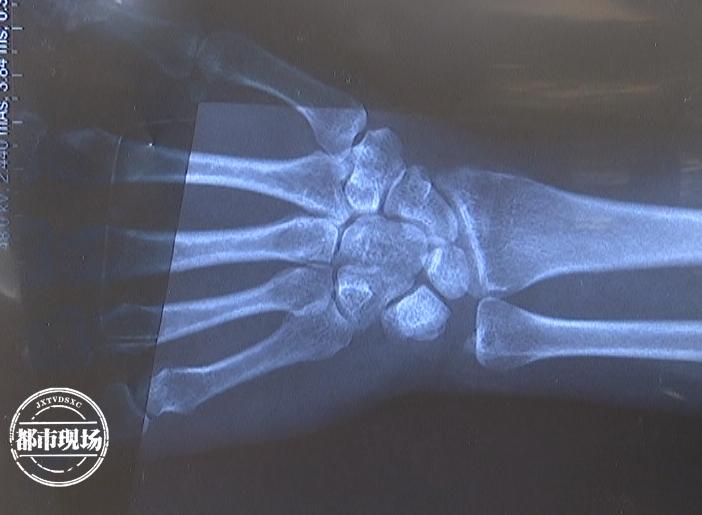

南昌市“米湯記憶”餐館服務(wù)員 蔡女士:因?yàn)檫@打了石膏,到月底才能拆掉,就是說不能動了,生活不能自理,自己的日常都能很難,起碼要休息三個月了。